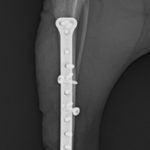

脛骨中央部らせん状骨折 階段で転んだワンチャンが、骨折をしてしまったので手術をしてほしいとの連絡があり対応しました。比較的、長い範囲でのらせん状骨折です。2本のポジションスクリューとプレーティングにより骨接合術を行いました。 症例カテゴリー 放射線治療整形外科軟部組織外科脳神経外科内科腫瘍外科救急・集中治療リハビリテーション科腫瘍内科内視鏡科脳神経科呼吸器外科中医・漢方猫の腎移植循環器科